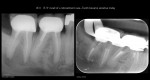

Very compliant patient—always made his recalls. Tooth has been asymptomatic for 15 years…and the periapical area had cleared—-now tender to biting and patient has an ache….No evidence of any occlusal issues. Will start the retreatment…again. Ugh….. gbc